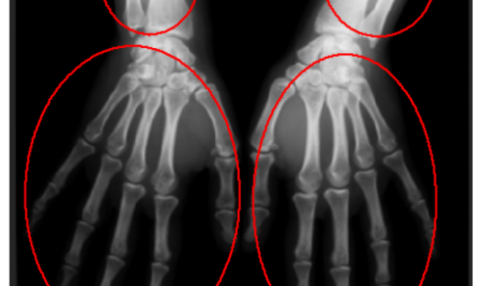

- پردازش و تحلیل تصاویر پزشکی